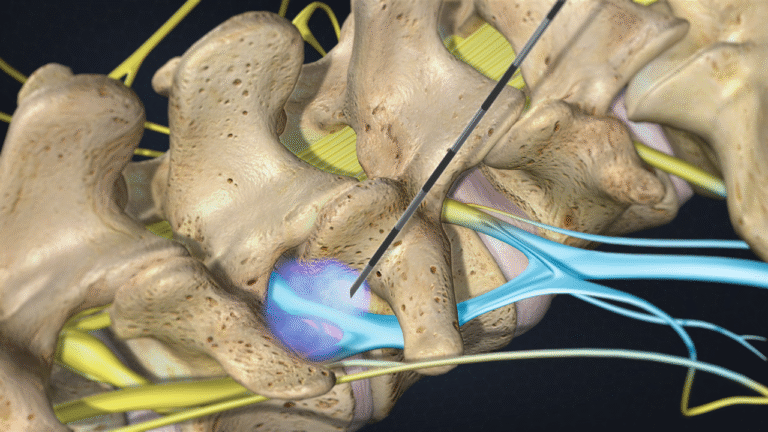

- Procedure mini-invasive

Mal di schiena

Il dolore lombare è una condizione molto frequente. Può avere diverse cause, come problemi muscolari, articolari o discali, e spesso limita le attività quotidiane.